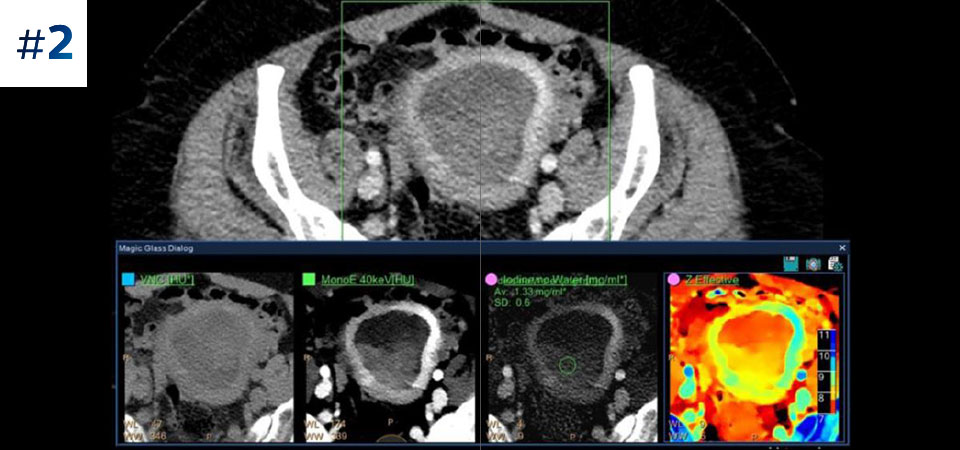

Vai oltre la TC convenzionale. Scopri come i risultati con diversi strati del detettore spettrale possono migliorare l'affidabilità diagnostica.

Osserva la differenza tra la TC basata su detettore spettrale e la TC convenzionale